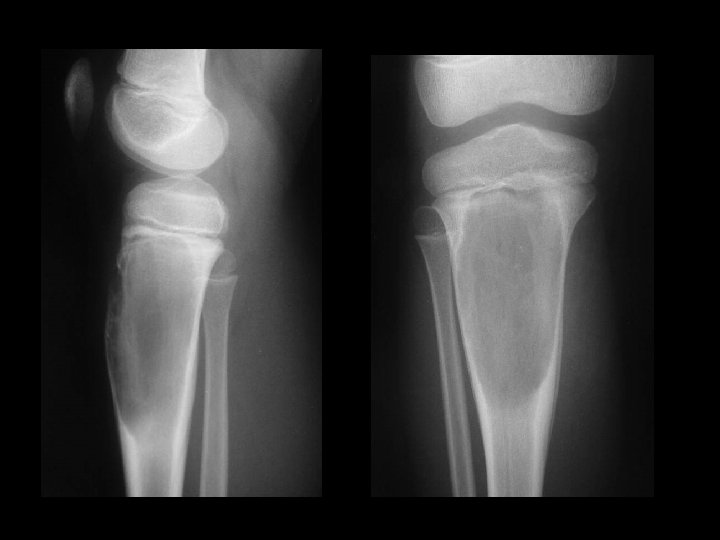

A 14 year old boy presents with pain and a mass above the knee. Take a look at the AP and lateral radiographs first.

Osteochondroma Chondrosarcoma

Malignant transformation Usually occurs above the age of 40 years. Sudden increase in size. Swelling becomes painful.